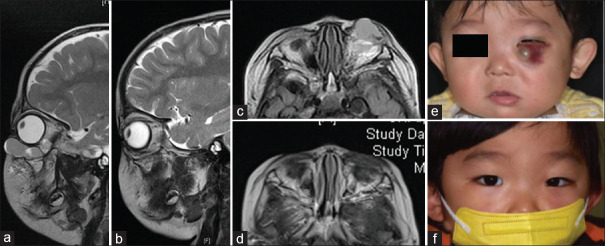

Orbital venous-lymphatic malformations (VLMs) are complex vascular anomalies that pose significant challenges to ophthalmologists due to their diverse clinical manifestations and the difficulties inherent in their therapeutic management, particularly given their proximity to critical orbital structures. This narrative review synthesizes the current knowledge on the classification, pathology, molecular mechanisms, imaging characteristics, and therapeutic strategies for VLMs. Historically misclassified as orbital lymphangiomas, VLMs are now recognized as complex malformations comprising interconnected venous and lymphatic components, with the potential for significant complications, including proptosis, visual impairment, and esthetic disturbances. Recent molecular insights have revealed critical pathogenetic mechanisms, particularly mutations in the PIK3CA gene that activate the phosphatidylinositol 3-kinase (PI3K)/AKT/mammalian target of rapamycin transduction network, alongside the upregulation of vascular endothelial growth factor (VEGF)-mediated signaling. These aberrations not only illuminate the disease etiology but also present promising therapeutic targets. Contemporary management strategies emphasize a multidisciplinary approach, with sclerotherapy emerging as a particularly promising intervention. Sclerosing agents such as bleomycin and pingyangmycin typically yield effective treatment outcomes with relatively favorable safety profiles. Surgical excision is reserved for accessible lesions but often requires adjunctive therapies due to the infiltrative nature of VLMs. Emerging treatments targeting molecular pathways, including PI3K inhibitors and anti-VEGF therapies, show promise in refractory cases. As our understanding deepens, clinicians can now offer more personalized interventions that consider factors such as lesion location, extent, architecture, and hemodynamic characteristics, thereby minimizing morbidity and optimizing clinical and aesthetic outcomes.